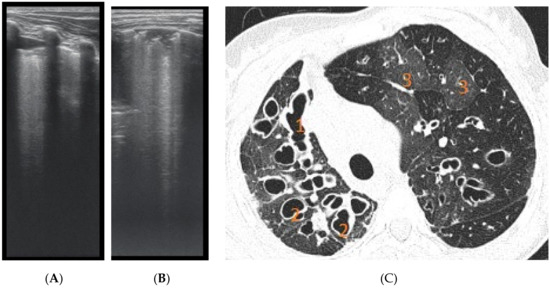

The artefacts used to define the pathological elements were as follows (Table 1): the presence of A lines—normal aspect = 0 points; less than 3 B lines, thin (< 2 mm in width)/intercostal space = 0 points; more than 3 distinctive B lines or 1 coalescent B line = 1 point, quantifying interstitial inflammation or small bronchiectasis (Figure 1) confirmed by CT (Figure 2); more than 2 coalescent B lines = 2 points, suggestive of alveolo-interstitial inflammation or mucus plugging with loss of aeration; either bronchial wall thickening or subpleural consolidation < 1 cm = 3 points, associated with the absence of A lines quantified either as small atelectasis or cystic bronchiectasis with mucus plugging; subpleural lung consolidation > 1 cm, without bronchogram = 4 points; quantified atelectasis (Figure 3)/consolidation with bronchogram = 5 points.

The right hemithorax of the same patients revealed the presence of B lines for cylindrical bronchiectasis via LUS (Figure 5).

Figure 1. LUS image shows B lines > 3, LUS score = 2. The corresponding CT image (Figure 2) shows bronchiectasis.

Figure 2. CT reveals (1) peripheral cylindrical bronchiectasis with mucus plugging.

Figure 5. LUS: coalescent B lines, with a very small subpleural consolidation (2 points) and 2 coalescent B lines (2 points), corresponding to mucus-filled varicose bronchiectasis; examination of the same patient’s right posterior hemithorax.